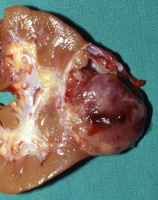

Der Tumor verdrängt zumeist deutlich abgegrenzt das residuale Nierengewebe.

Auf der Schnittfläche ist der Tumor von gelbbrauner bis grauer Farbe mit einzelnen Einblutungen. Zystische Anteile und Nekrosen kommen vor sowie oberflächlich glatte, knotenförmige Strukturen, ähnlich einem Rhabdomyosarkom (Abbildung 1a-d).